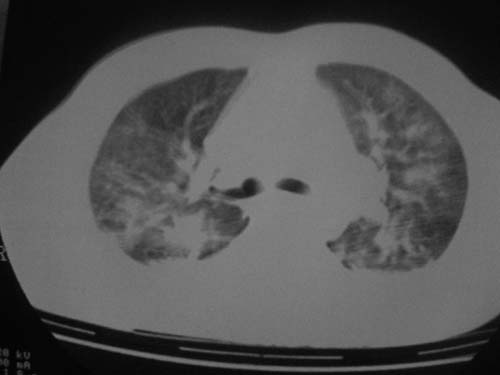

这是第五天拍的ct,纵隔窗我没都传,实在是太费时,请教各位老师,此病人有肺水肿吗?帮忙分析一下

1)双侧创伤性湿肺。2)双侧胸腔积液。

结果:病人刚入院水电解质紊乱,治疗期间大量输液,而且速度较快,正如4.5楼那样说的引起肺水肿,对症治疗后病情好转,